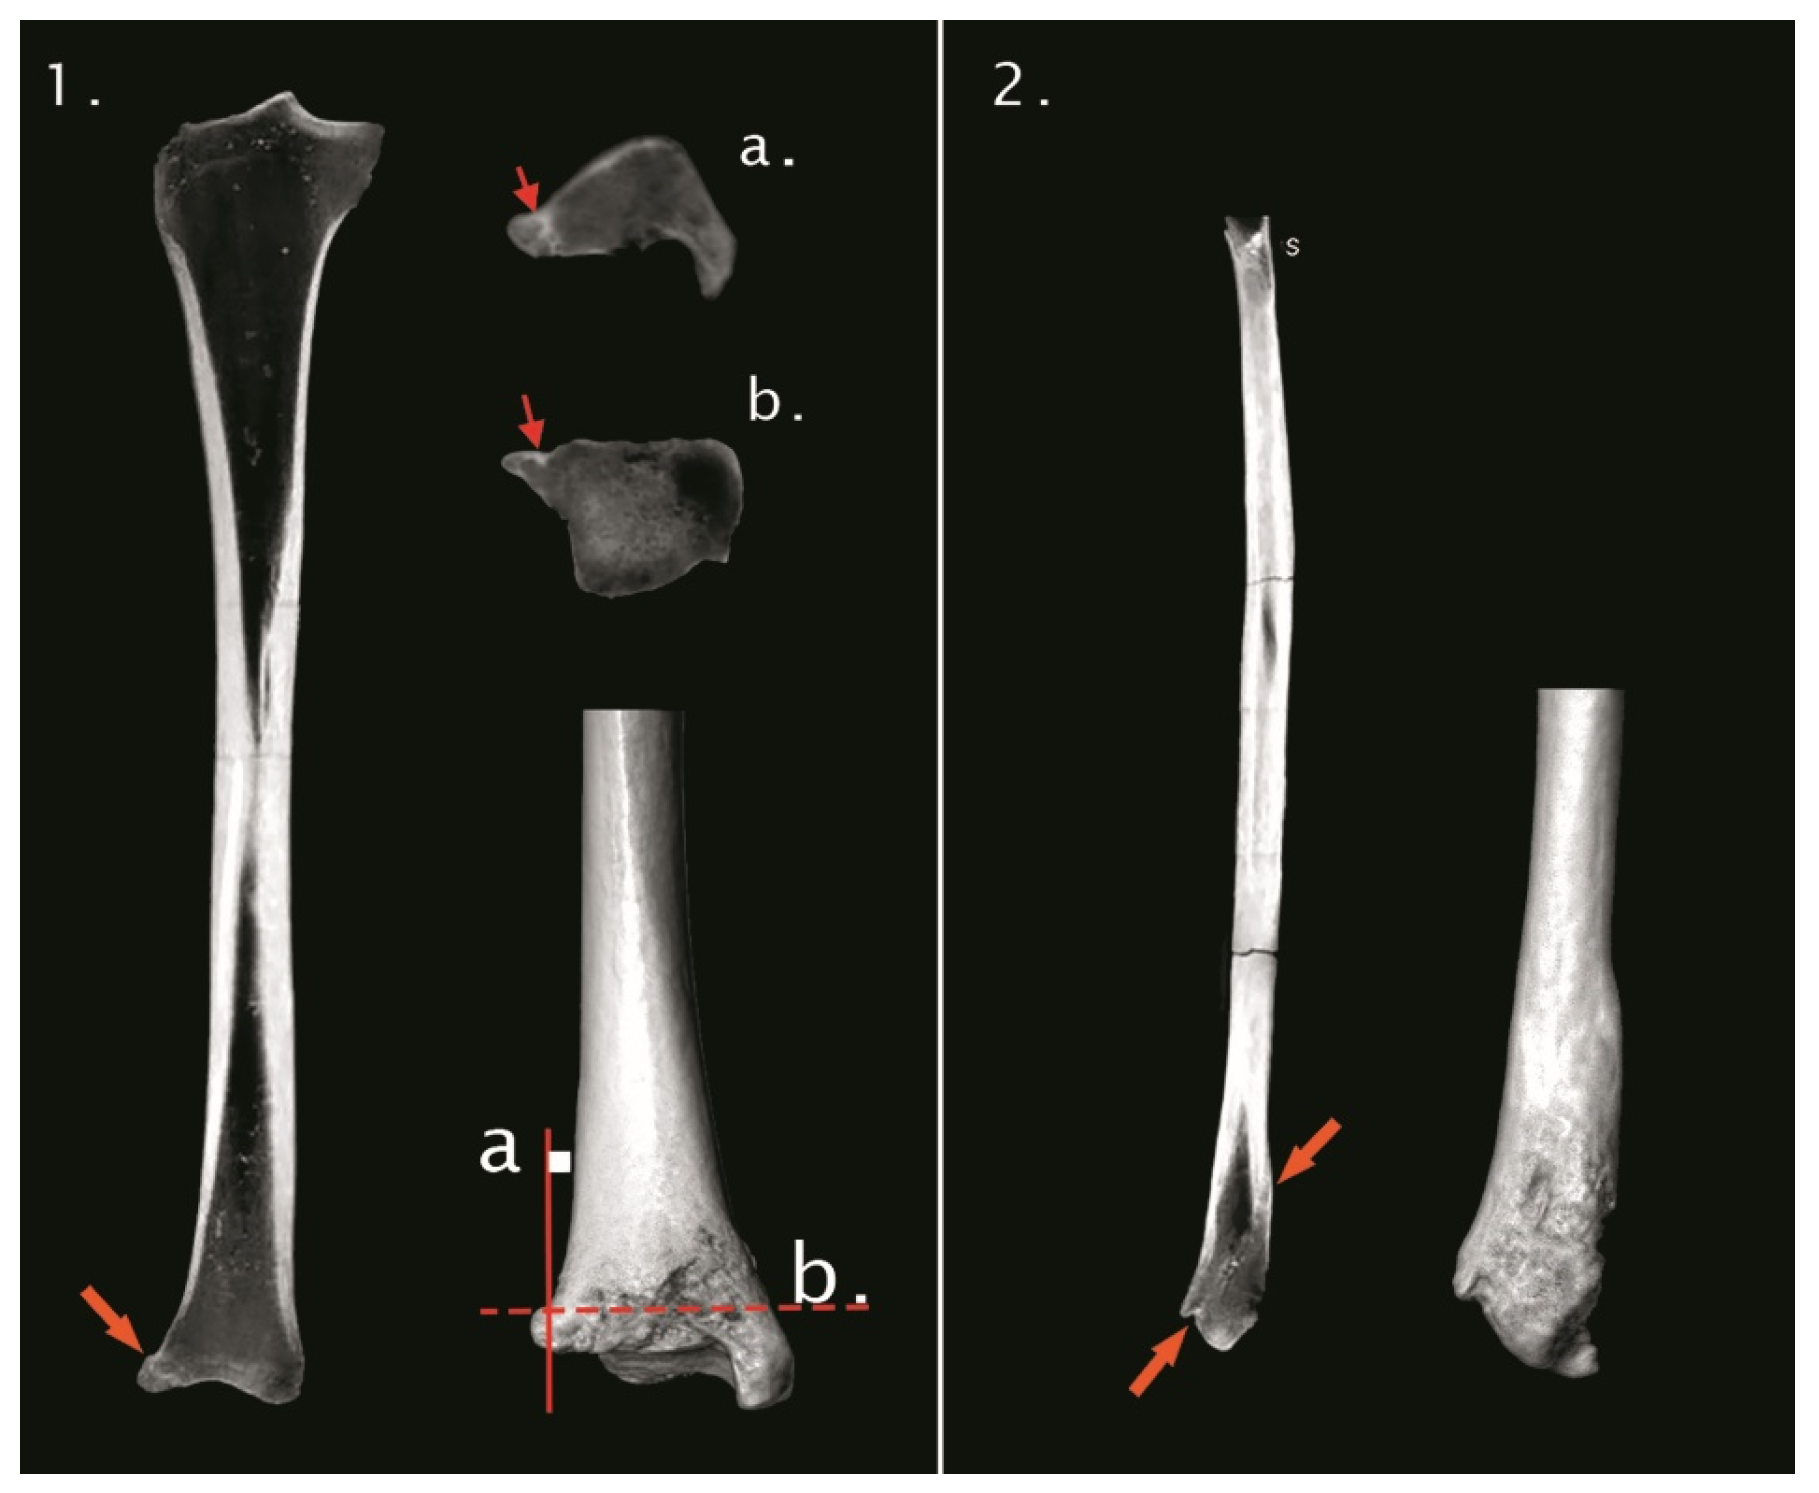

The study aims to reconstruct the life history of an individual whose skeleton was recovered during the excavation of the late medieval Pauline monastery of the Blessed Virgin Mary on Moslavina Mountain, Croatia. The monastery was one of the most important ecclesiastical centres in continental Croatia during the 14th/15th centuries CE and was abandoned between 1520 and 1544 due to fear of imminent Ottoman attacks. The inscription and coat of arms on the tombstone of a tomb located in the chancel, next to the main altar, indicate that the skeleton belongs to Sofia Kaštelančić née di Prata (di Pordenone), a member of Croatian late medieval high-ranking nobility. We conducted a conventional bioarchaeological study, carbon and nitrogen stable isotopes analysis, paleoradiological imaging (CT/CBCT scanning), and three-dimensional facial reconstruction. The skeleton belongs to a middle-aged woman between 40 and 50 years old with an estimated stature of about 161 cm. Numerous pathological changes, such as ante mortem tooth loss, caries, abscess, linear enamel hypoplasia, dysodontiasis, and osteophytosis were observed, with the most notable pathology being the fracture of the right ankle, a fact also confirmed by CT scanning. Carbon and nitrogen isotopic values are consistent with a terrestrial diet based on C3 plants with no marine input, and the consumption of large quantities of animal-based proteins. Three-dimensional facial reconstruction made it possible for the first time in over 500 years to obtain the approximate physical appearance of the individual. The presented results are consistent with the hypothesis that the skeleton probably belongs to Sofia Kaštelančić. Nevertheless, none of the observed osteological traits are individually or collectively diagnostic of Sofia, so, in the absence of individualising evidence, the identification remains hypothetical rather than demonstrative.